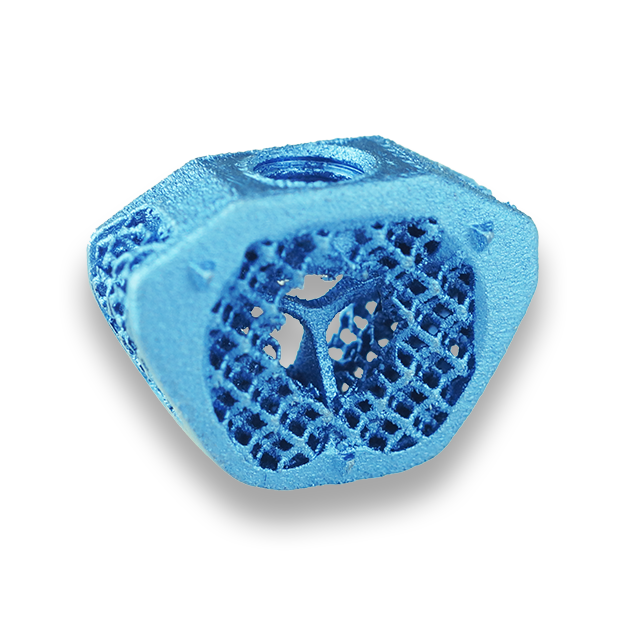

Each LeiCAGE implant is 3D-printed from medical-grade titanium, featuring a porous lattice structure (dodecahedron construction) that encourages rapid bone ingrowth and long-term osseointegration. This design replicates cancellous bone architecture, facilitating direct biological fusion between vertebral bodies and promoting stable load transfer during the healing process.

LeiCAGE implants are available in multiple sizes to accomodate anatomical variations and surgical requirements. Their anatomically contoured geometry ensures optimal endplate contact and uniform force distribution, reducing the risk of subsidence and maximizing stability.